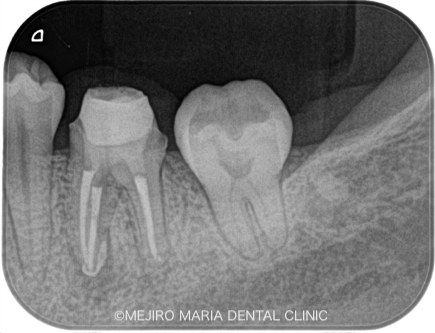

患者様は、数年前にひどい虫歯のために根管治療を受けておられましたが、数日前より左下が腫れ始め、瘻孔(フィステル/溜まった膿を排出する穴)ができたと来院されました。

レントゲンで診査すると、左下6番(第一大臼歯)の近心根(歯の根のより中心に近い部分)に根尖性歯周炎が確認でき、腫脹の原因は根尖性歯周炎であると診断しました。

また、同じ部位の根尖に、透過性の異なる充填物(赤丸)が確認できました。これは、以前の根管治療で使用していた器具が根管内で折れて、そのまま取り残されている状態です。

このように、治療中に折れた器具のことを歯科では「破折ファイル」と言い、トラブルケースの1つとして扱われます。このように細く長い根管で破折したファイルは、再治療の際に根管を洗浄するための器具の到達を困難にし、また、破折ファイルを除去するための器具のアプローチも難しいため、結果として根尖部の洗浄が不十分になってしまいます。